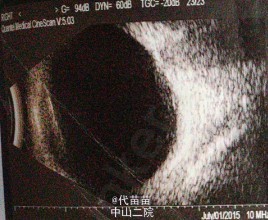

体格检查:专科检查:左眼上睑轻水肿,结膜混合充血明显,瞳孔区白色反光,对光-,角膜轻水肿 辅助检查:1.右眼玻璃体混浊,球壁不光滑声像2.左眼内实性占位性病变声像